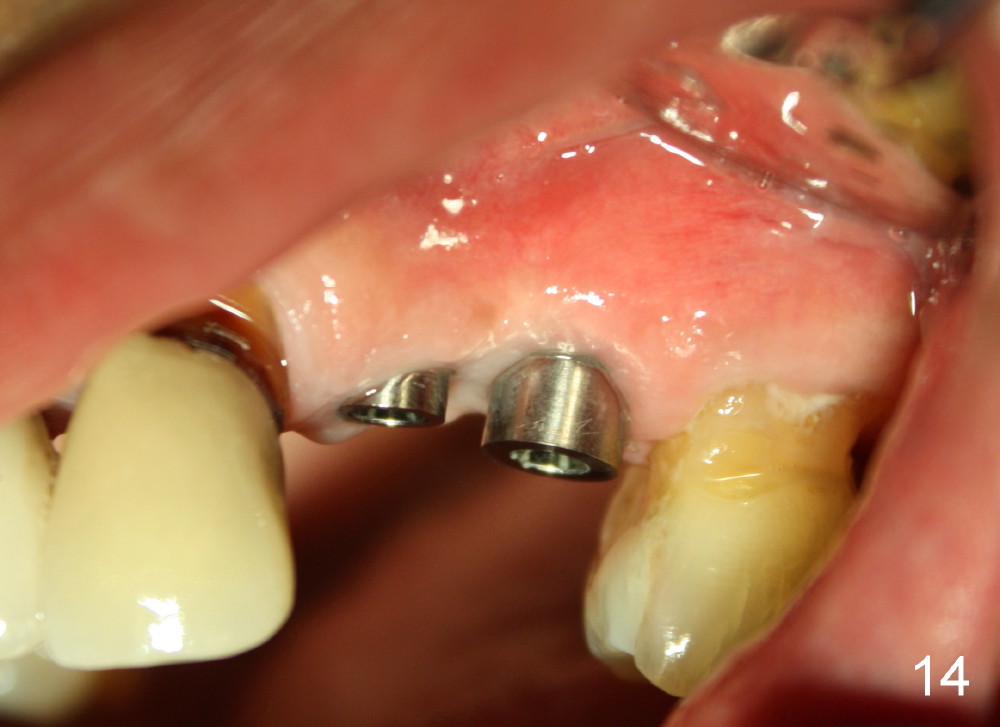

Three month follow-up shows that the gingiva and bone heal around these two implants (Fig.13-15). Crowns are cemented 4.5 months postop (Fig.16). There is no or minimal bone loss 9 months post cementation (Fig.17, as compared to Fig.15). The bone is stable around the implants 18 months post cementation (Fig.18 panoramus). Root canal therapy is done at #14 between the last follow up appointments.